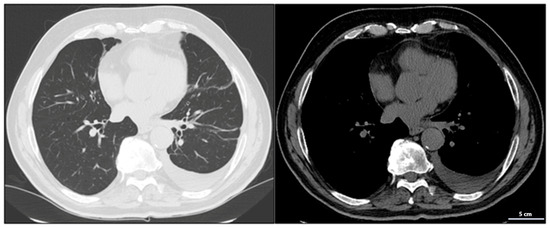

A chest CT scan performed in February 2023 confirmed the presence of a 35 mm solid nodular mass with irregular margins in the apical segment of the lower left lung lobe (Figure 2).

Figure 2.

Chest CT showing a large solid nodular formation in the lower left lung lobe.